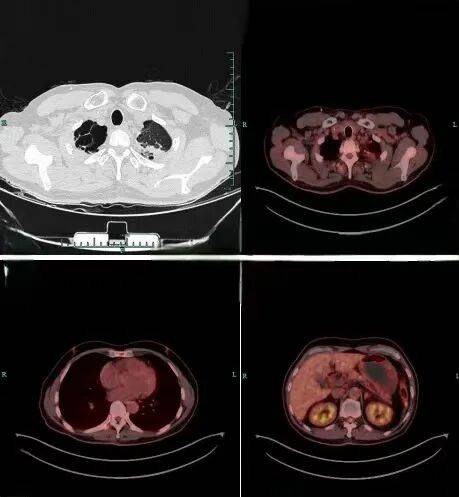

全身PET:左肺尖软组织密度肿块(FDG代谢增高,考虑肺癌)、左侧锁骨区肿大淋巴结(FDG代谢增高,考虑转移)、T8右侧横突骨质密度局灶性减低(FDG代谢增高,考虑转移),左侧肾上腺增粗伴FDG代谢增高(转移不除外);

图中为治疗前肿瘤的位置

复查胸部增强CT及全身PET显示,左肺尖病灶较前明显退缩,FDG代谢略增高(较前显著减低),原左侧锁骨区转移淋巴结基本消失,T8右侧横突转移灶FDG代谢未见增高,肿瘤活性受明显抑制;

图为治疗后的效果:病灶明显缩小代谢降低